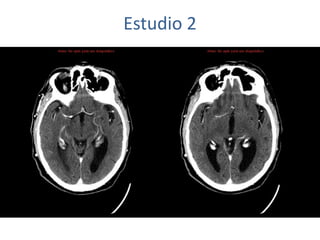

Estudio 2

• Estudio sin y con contraste, con reconstrucciones sagitales y coronales

del estudio con contraste.

Se observa una lesión ocupante de espacio en lóbulo frontal derecho que

presenta un tamaño de 18 x 32 x 22 mm (cc x ap x tr), bilobulada, no del

todo bien delimitada, con realce en anillo irregular, con hipocaptación

central, probablemente por necrosis, y asociada a un extenso edema

vasogénico con efecto masa tanto sobre los surcos de la convexidad

como sobre la cisterna insular, el sistema ventricular y la línea media,

esta última con un desplazamiento de 5 mm a la altura del septo

interventricular.

No se aprecian otras lesiones focales intra o extraaxiales de significación

patológica.

Habría que considerar como primera posibilidad que se tratase de una

lesión metastásica, por bien un tumor primario, aunque no se puede

descartar otras opciones, sin imprescindible correlación con la clínica y

con sus antecedentes.